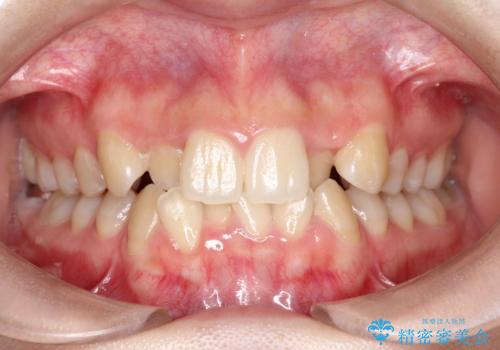

前歯のデコボコと開口を改善し、美しい口元へ

担当医 河口智英